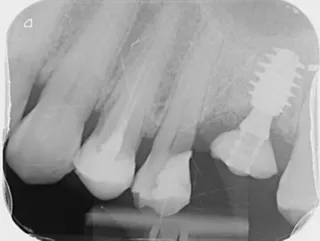

11a. 11b. Radiographs of the SSA in place and scan body for digital impressions.

11a

11b